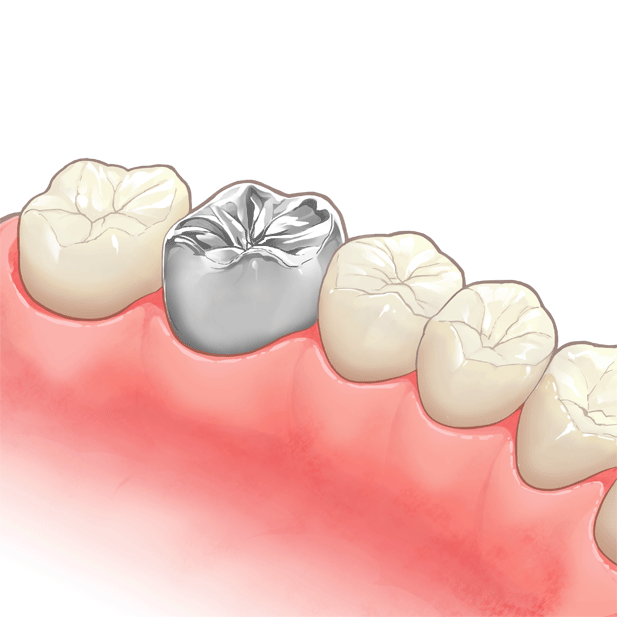

⑥ 前回詰めた綿花の状態を確認して、良い状態なら、「根管充填剤」(マスターポイント・アクセサリーポイント)というお薬を、余分な空間がないように根っこに詰めます。

⑥ 前回詰めた綿花の状態を確認して、良い状態なら、「根管充填剤」(マスターポイント・アクセサリーポイント)というお薬を、余分な空間がないように根っこに詰めます。 Q1.痛みはありますか?

Q1.痛みはありますか? ② 次に、「根管長測定器」という機械を使い、根っこの長さを正確に測ります。

② 次に、「根管長測定器」という機械を使い、根っこの長さを正確に測ります。

⑤ 次に、仮詰めをします。

⑤ 次に、仮詰めをします。 虫歯が神経まで達して炎症を起こしているので、人によってはズキズキとした痛みを感じる方もいます(>_<)

虫歯が神経まで達して炎症を起こしているので、人によってはズキズキとした痛みを感じる方もいます(>_<)